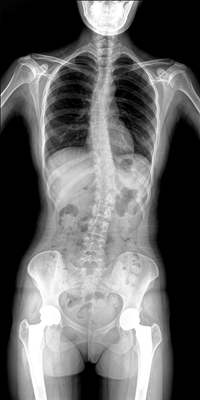

临床需要对患者的脊柱情况有全面了解,故而术前术后均需要均需要借助DR拍摄X光片便于分析病情、明确诊断及术后观察治疗效果。大视野动态DR可以对患者的脊柱进行长尺寸摄影,一次拍摄就能获取完整的脊柱全景图像。诊断医生通过拍摄后的影像测量全脊柱的生物角度、Cobb角等,为脊柱侧弯的畸形矫正患者术前术后的检查提供重要的诊断依据。

通过大视野动态DR进行全脊柱摄片,其得到的影像密度均匀、清晰、接缘处过渡自然。且操作更加便捷,不需要二次摄片然后进行图像拼接,拍摄时间短,效率高。在减少辐射剂量的同时也能为临床医生带来更精确的诊断信息。非拼接影像可保证双腿测量(如力线)数据的准确性,有效避免摄影信息的丢失。给手术医生提供准确的术前诊断数据,提高手术成功率。

综上所述,大视野动态DR进行全脊柱成像能够清晰的呈现骨关节结构,可以在全景脊柱图像基础上对角度值进行测量,能够很好的反映骨骼的真实比例与长度,为临床诊断和治疗提供了更精确的数据,有着重要临床应用价值。